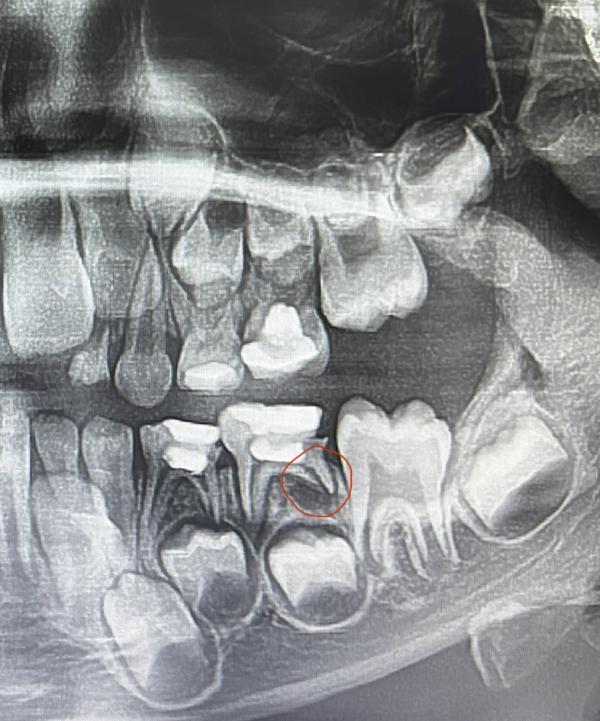

Посоветуйте,что делать,ситуация такая,дочери 6 лет,вчера отвалилась пломба с пятерки внизу,мы эту пломбу еще два года назад в бебиленд ставили, и в бебиленд ей не до конца прочистили каналы, так вот сегодня ездили на консультацию в другую клинику насчет этого зуба,нам сказали что под корнем образовался гнойный мешочек (на фото обвела красным) ,и зуб у нее немного болит из-за этого,т.е есть воспаление,нам предложили прочистить каналы,заложить лекарство и через неделю поставить пломбу,но они не дают гарантию на пломбу,либо удалять и ставить распорку.Я вот думаю корни почистят,лекарство положат,а если потом будет отек,нам же всё-равно придется удалять зуб,а если нет,поставим пломбу,и будем ходить пока пломба не отвалится,или пока зуб не выпадет,а выпадет он не скоро,либо удалить сейчас,и распорки поставить.